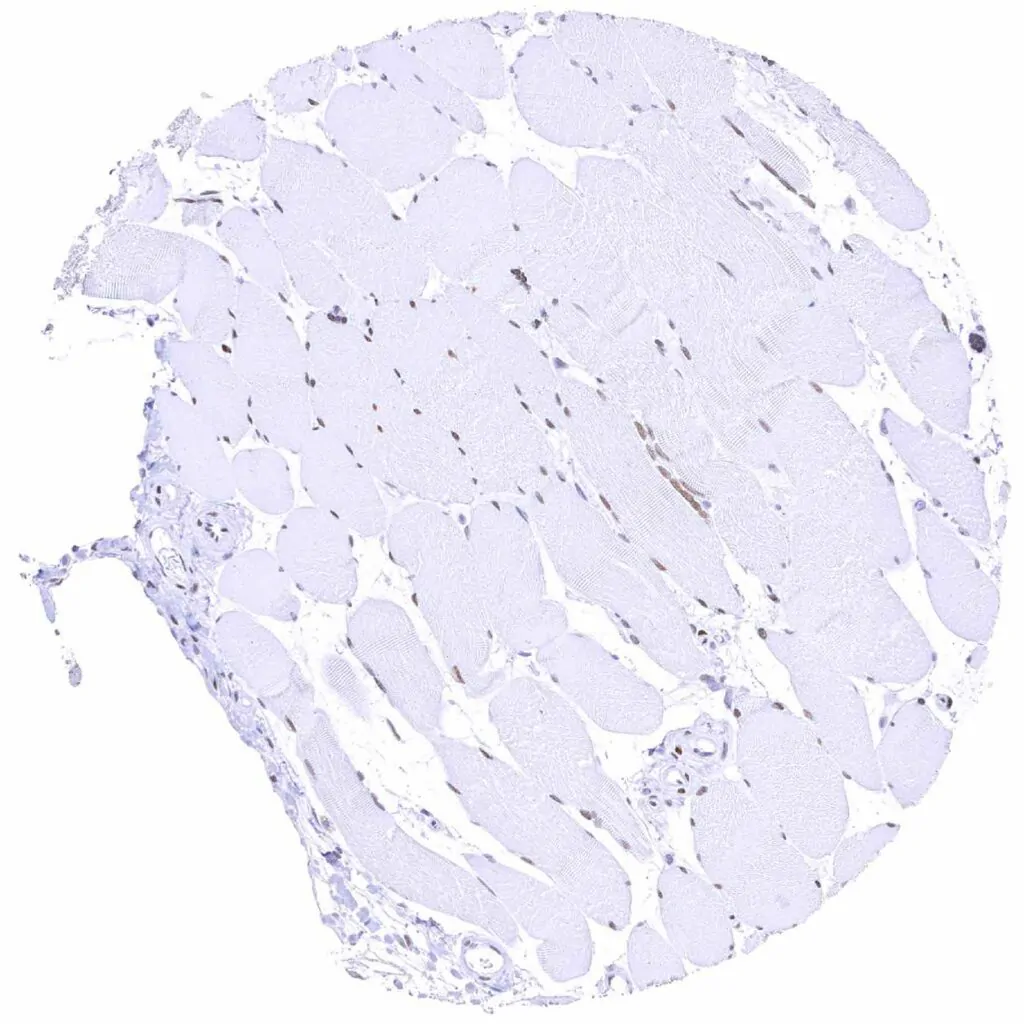

Heart muscle

Skeletal muscle – Moderate to strong TLE1 positivity of skeletal muscle cells